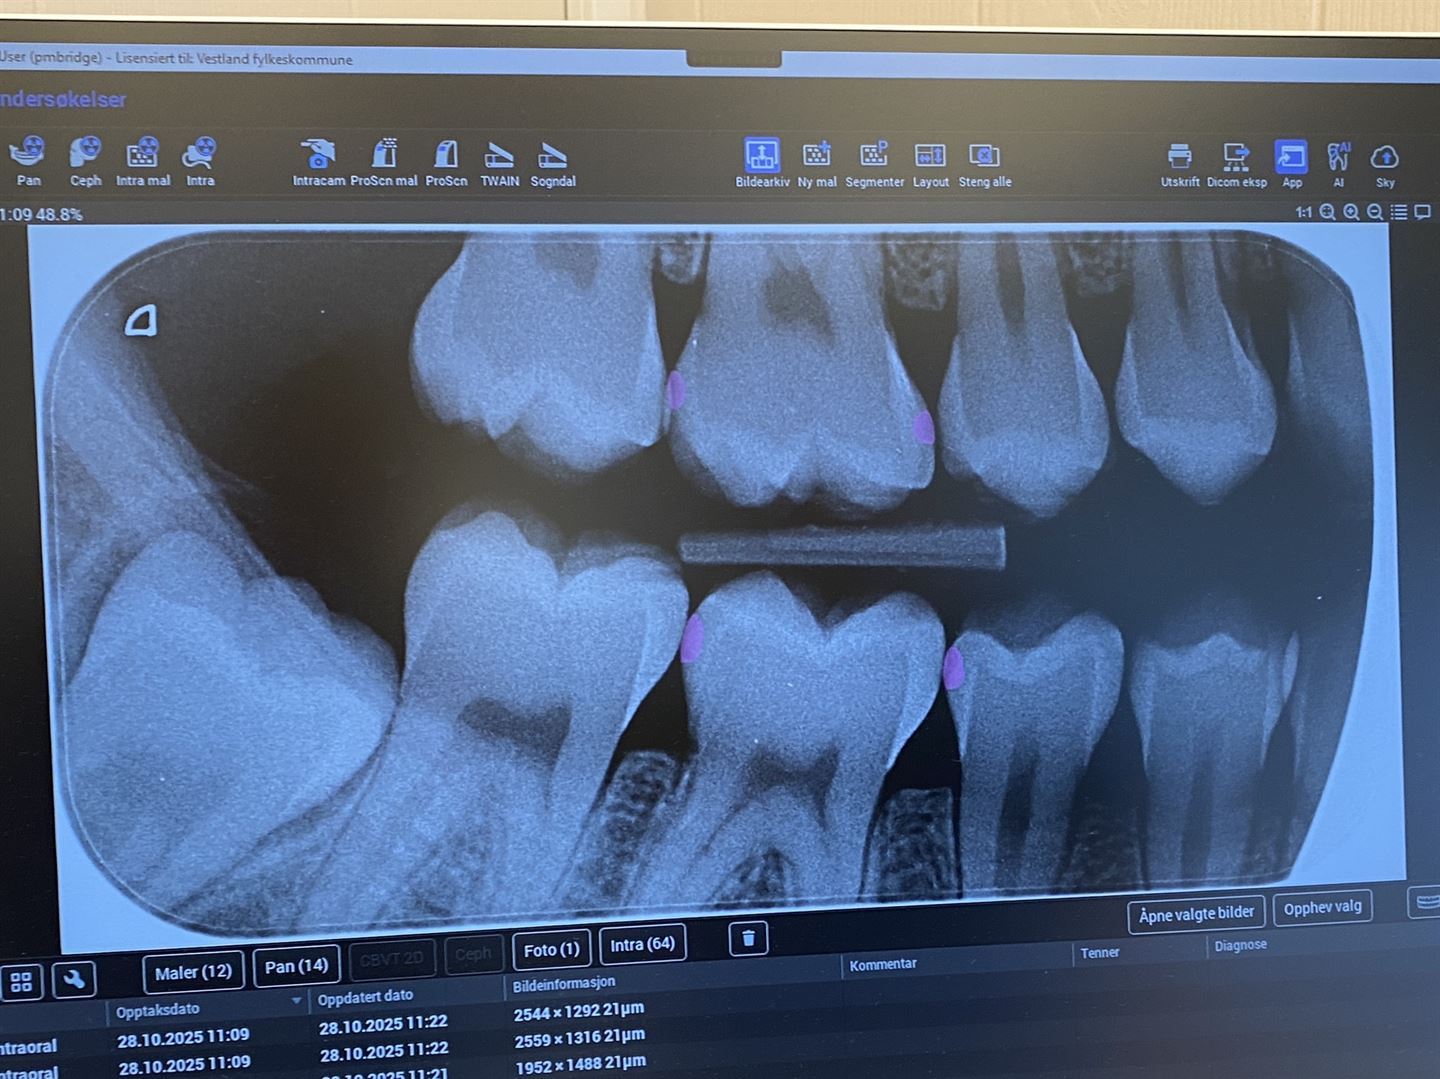

røntengenbilete av tenner

ROSA = KARIES: Det er lett å sjå der KI-verktøyet finn karies på ei tann. Området blir nemleg rosa. Foto: Birthe Finstad, Vestland fylkeskommune.

Analyseringa tek om lag 30–40 sekund, og resultatet blir vist som fargefelt på biletet, rosa område der KI-en ser teikn til karies, eller grøne område der det er forventa å finne tannstein. Fordi bileta på KI-analysen tydeleg viser med farge kor det er karies eller tannstein, gjer det det enklare for pasientar å forstå kva tannlegen ser på røntgenbiletet.